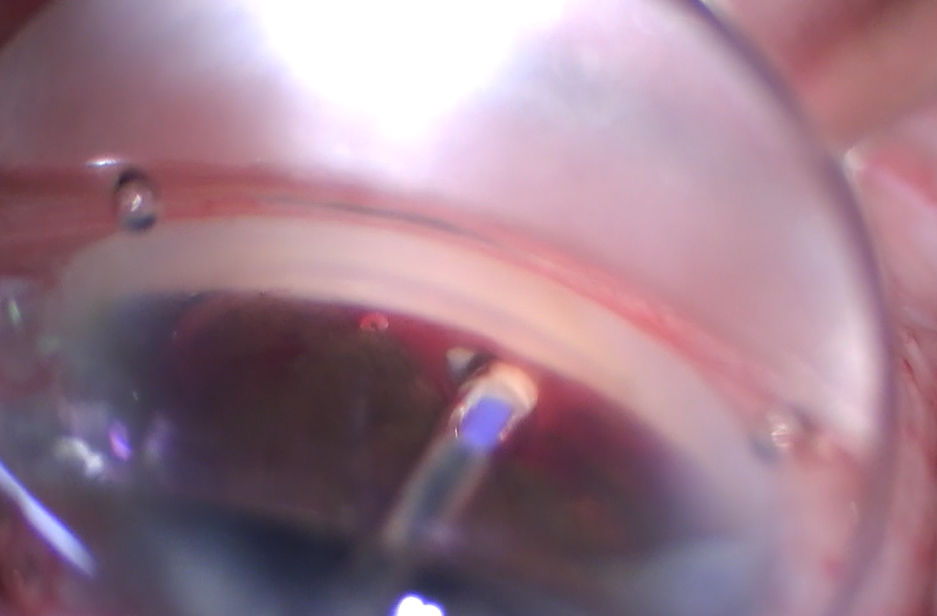

A side port incision and clear corneal temporal incision (Dr. Provencher uses a 2.4 mm keratome) is created. Then, she said the AC is filled with cohesive viscoelastic, adding that this is a better tamponade of bleeding. โUnder a gonioscopic view, you create a 1-clock hour cleft by strumming posteriorly on the scleral spur with a cannula or cyclodialysis spatula,โ Dr. Provencher said. โThink of the cannula (or spatula) following the curve of the sclera. You will see the white scleral back wall if you are in the right space. Fill this space with additional viscoelastic. You then enter the AC with the AlloFlo Uveo, insert it into the cleft, and retract the sleeve, which deploys the stent.โ She added that you want about 0.5 mm of stent in the AC, and the position can be adjusted easily by tapping it in farther with the inserter or pulling it out with a cystotome. โYou can then expand the cleft and add another stent at the other margin of the cleft,โ she said. โCurrently, I use two stents with 1โ1.5 stent widths in between. Remember, these stents are designed primarily as scaffolds, though they do transmit fluid. You may encounter bleeding, but it rinses out with I/A.โ She added that postoperative hyphema is rarely significant.

For cleft creation (if not being done with the stent handpiece or inserter), there are several instruments that can be used, Dr. Schehlein said. โSome surgeons may choose to create a cleft simply with the viscoelastic cannula, however, a Koch spatula or cyclodialysis spatula can also be suited for adequate cleft creation,โ she said.

Dr. Schehlein also cautioned that cleft creation can be difficult, and it may feel counterintuitive. However, she said that the structure of the cleft is important in procedure success. โVisually, surgeons should see the underside of the scleral wall (white),โ she said. โAfter cleft creation, surgeons can dilate the cleft with viscoelastic to enlarge the cleft and tamponade heme.โ